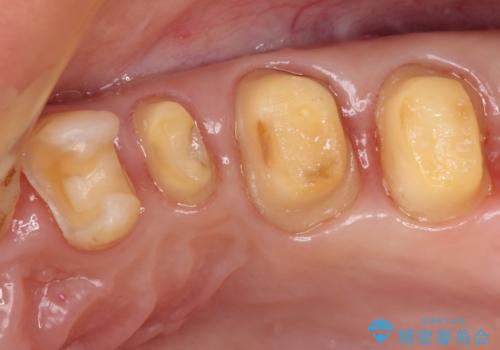

- 奥歯の銀歯をセラミックの白い歯にして、しみる症状も改善したいとのことで来院された患者様です。

知覚過敏の症状が強い歯と、銀歯の範囲や銀歯の下のむし歯が大きい歯は、インレー修復では対応が難しいためオールセラミッククラウンで、インレー修復で対応が可能な歯ではセラミックインレーにて修復することとしました。